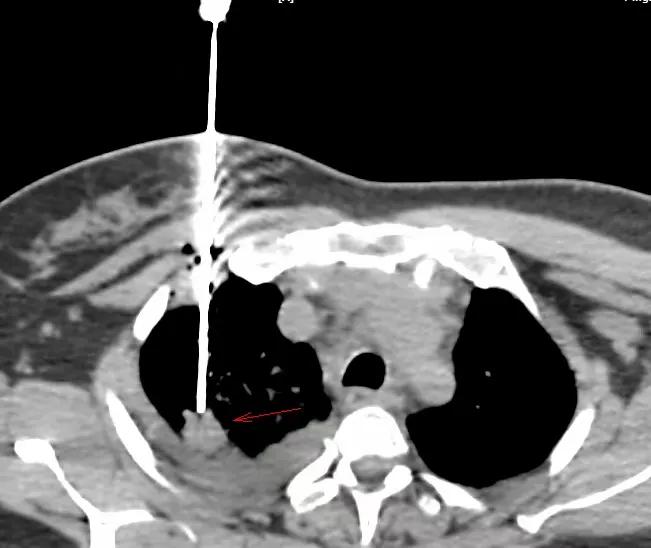

改用仰卧位,从前胸壁穿刺有穿刺路径

穿中结节,到边缘即可,这样可取材整个结节穿刺方向上的组织。